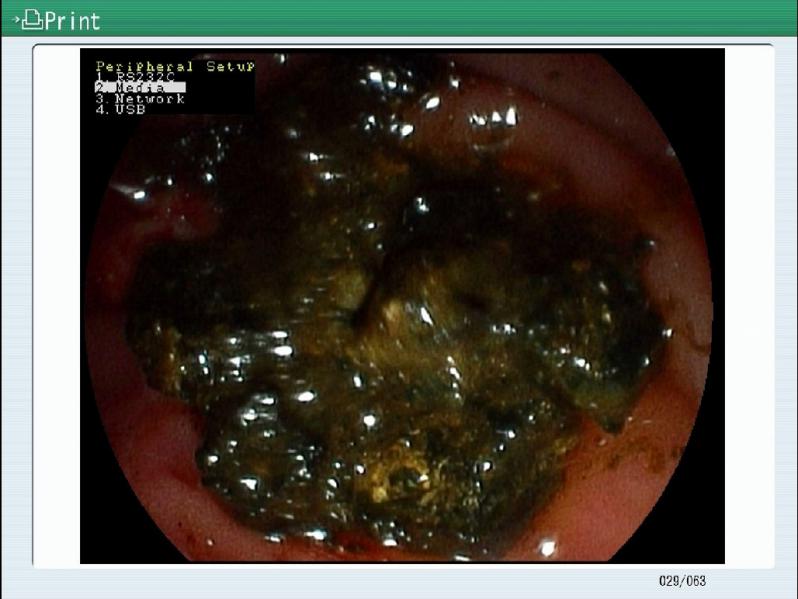

近日一位患者,突发腹痛、寒战高热的患者到茂名市人民医院消化内一科就诊。消化内科吴振华主任为患者完善相关检查,结果发现患者胆总管多发结石,且出现梗阻性黄疸。刻不容缓,消化内科吴振华主任团队马上为进行手术,手术过程顺利。目前,患者已康复出院。

吴振华主任表示,ERCP是目前消化内镜操作中难度最大的技术之一。对于胆道系统结石,一般不建议排石治疗,因为排石过程中若巨大结石出现嵌顿造成胆管梗阻,诱发胆管炎或急性胰腺炎,非常危险。ERCP术,患者不需要开刀、痛苦小,安全性高、并发症少,还能保留胆管系统完整及生理功能,已成为目前胆总管结石的首选治疗方法。还有胆管结石易于复发,如再发结石还可以选择ERCP取石,而开腹再次手术的困难相对较大。